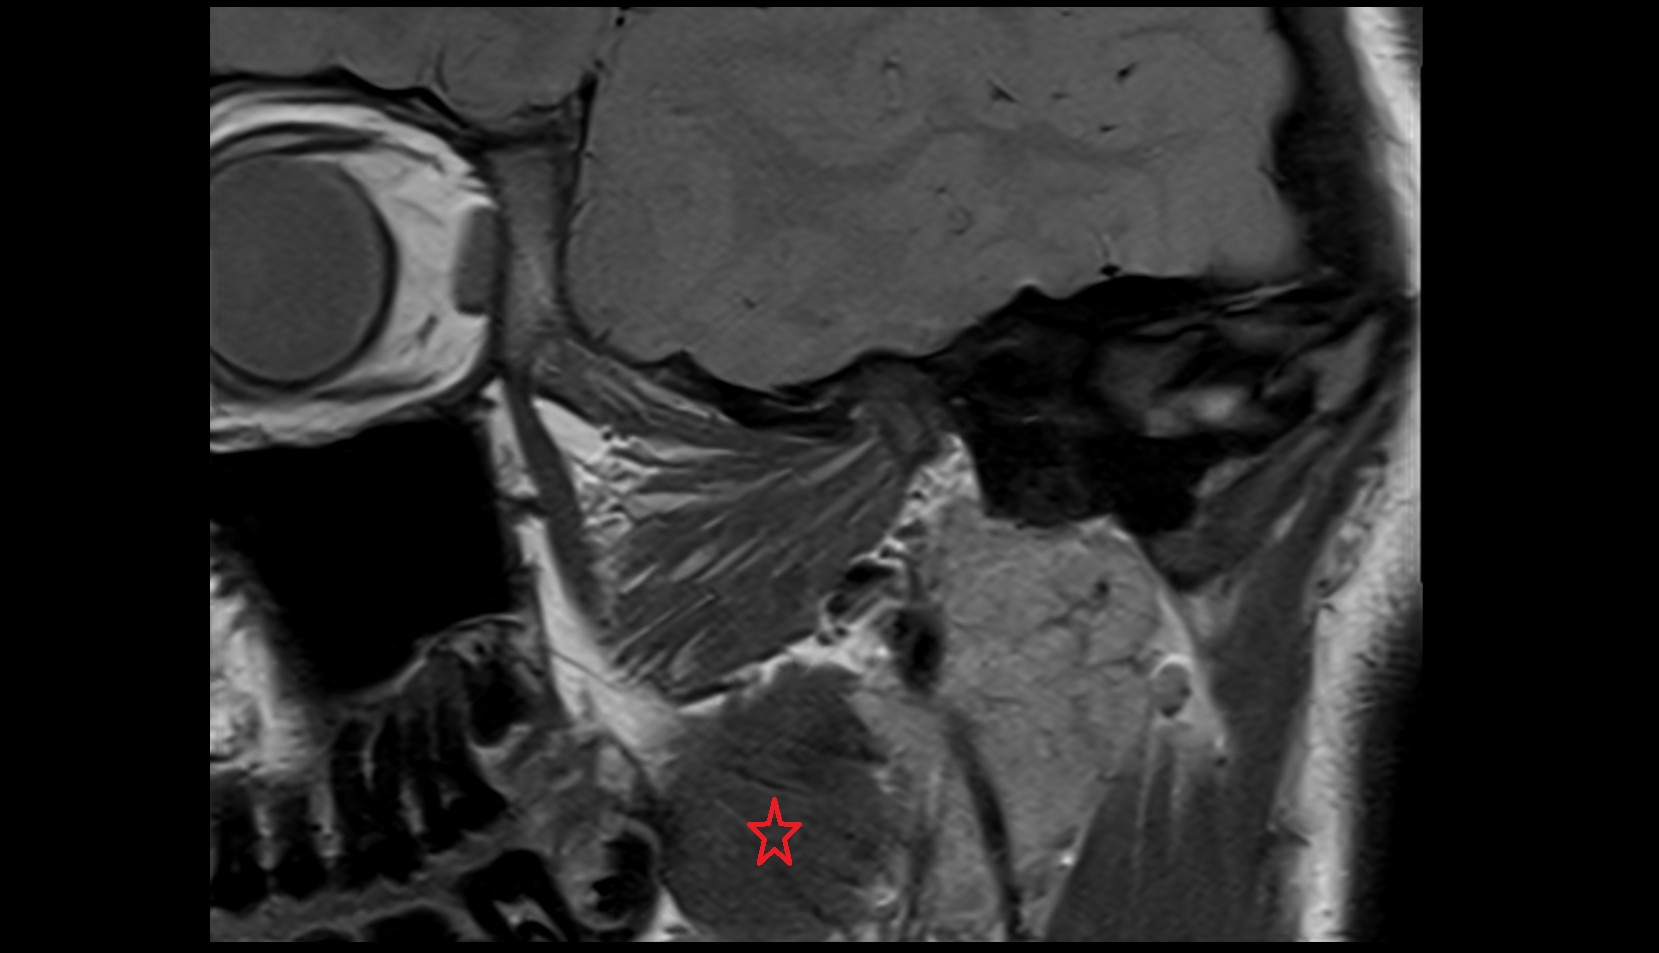

- Temporomandibular joint

- Mandibular condyle

- Mandibular fossa

- Superior head of lateral pterygoid muscle

- Inferior head of lateral pterygoid muscle

- Lateral pterygoid muscle

- Masseter muscle

- Temporalis muscle